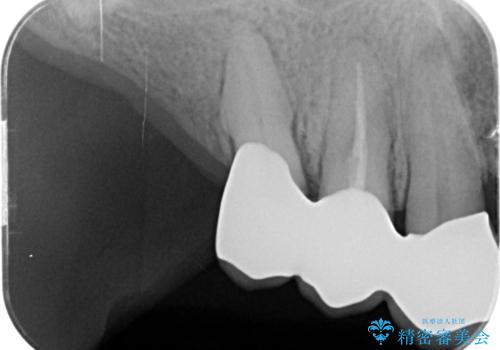

咬合の崩壊 金属床義歯で咬合機能の回復

- 「体調が悪く歯医者に行けない間にどんどん歯が悪くなってしまった、治療をしたい。」と咬合機能の回復を希望され来院されました。

「大規模な手術は避けたい。」と言う希望を鑑み、インプラントではなく残せる歯の連結セラミッククラウンの作製、金属床義歯を用いてしっかりと咬合機能を回復できるよう治療を進めます。

年齢と体調を考慮して、インプラントではなく入れ歯で咬合機能の回復を達成する治療計画としました。